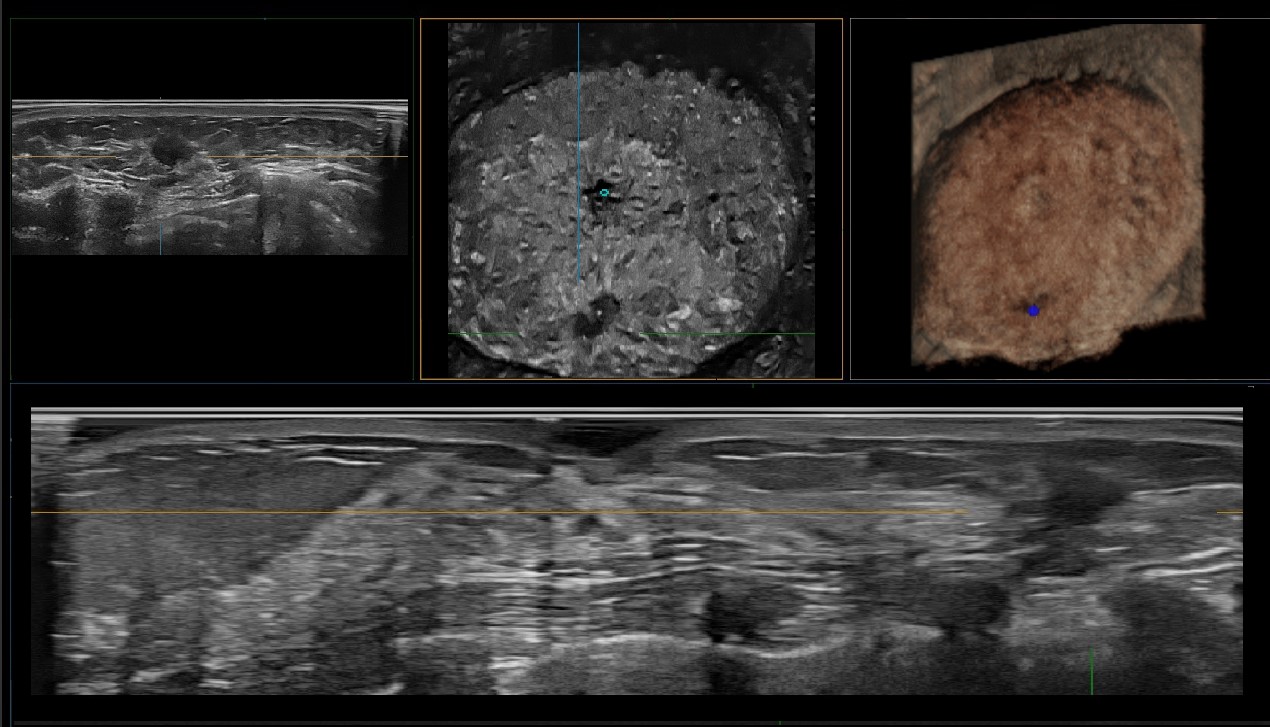

Full Volume Imaging and Coronal Section with High Clinical Value

IBUS acquires volume data from multiple sections to provide abundant information. The coronal section intuitively shows the anatomical information of breast tissue in a supine position during operation, which helps surgeon to perform more accurate surgical planning.

Lesion stereo images are generated from volume data rendering. It provides intuitive and detailed information for better observation and lesion localization.

Lesion correlation correlates the information obtained from different scanning positions and sections to avoid misdiagnosis.